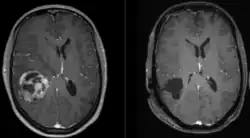

_im_MRI_preoperativ_und_postoperativ.png)

Surgery is the first stage of treatment for glioblastoma. An average GBM tumor contains 1011 cells, which is, on average, reduced to 109 cells after surgery (a reduction of 99%). Benefits of surgery include resection for a pathological diagnosis, alleviation of symptoms related to mass effect, and potentially removing the disease before secondary resistance to radiotherapy and chemotherapy occurs.[68]

The greater the extent of tumor removal, the better. In retrospective analyses, removal of 98% or more of the tumor has been associated with a significantly longer healthier time than if less than 98% of the tumor is removed.[69] The chances of near-complete initial removal of the tumor may be increased if the surgery is guided by a fluorescent dye known as 5-aminolevulinic acid.[70][71] GBM cells are widely infiltrative through the brain at diagnosis, and despite a "total resection" of all obvious tumor, most people with GBM later develop recurrent tumors either near the original site or at more distant locations within the brain. Other modalities, typically radiation and chemotherapy, are used after surgery in an effort to suppress and slow recurrent disease through damaging the DNA of rapidly proliferative GBM cells.[72]